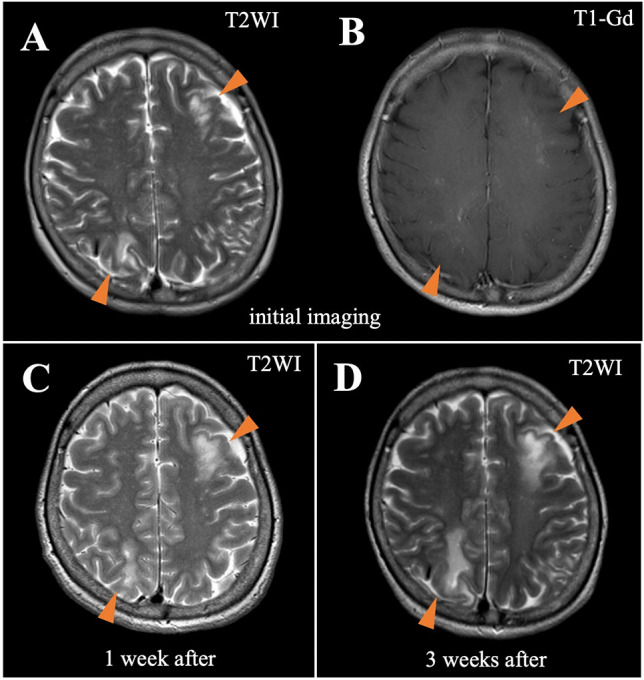

T2-weighted cranial magnetic resonance imaging (MRI) showed asymmetric, cortex-sparing white matter lesions in the left frontal, left parietal, and right parieto-occipital lobes, with weekly enlargements. Gadolinium-enhanced T1-weighted image showed partial enhancement in these brain lesions (Fig. 1A–C). Electroencephalography revealed repetitive spikes localized in the right parietal region (P4 max). Cerebrospinal fluid (CSF) examination showed no cells, a protein concentration of 33 mg/dL, an IgG index of 0.40, and positive oligoclonal IgG bands. JCV DNA was detected in the CSF using quantitative polymerase chain reaction (PCR) (166 copies/mL) at the National Institute of Infectious Diseases (Tokyo, Japan). Epstein–Barr virus, herpes simplex virus, cytomegalovirus, and varicella zoster virus were not detected by PCR. Serum and cerebrospinal fluid tests for Mycobacterium tuberculosis, Cryptococcus, syphilis, and HIV were also negative.

Fig. 1.

Magnetic resonance imaging of the head. T2WI indicates T2-weigted image; T1-Gd, gadolinium-enhanced T1-weighted image. T2-weighted image at the onset of progressive multifocal encephalopathy (PML) shows asymmetric, cortex-sparing white matter lesions in the left frontal and right parieto-occipital lobes (A). Gadolinium-enhanced T1-weighted image shows partial enhancement in these brain lesions (B). The lesions enlarge weekly, with a confluent pattern (C, 1 week after initial imaging; D, 3 weeks after initial imaging)

The patient fulfilled the diagnostic criteria for definite PML (Berger et al. 2013). Immune reconstitution was initiated before confirming the PCR findings. Tacrolimus was discontinued, and the methylprednisolone and everolimus doses were gradually tapered. There was no neurological deterioration, and the JCV DNA titer was reduced from 166 to 18 copies/mL 1 week after initiating immune reconstitution. As the lesions enlarged, the treatment was switched from prednisolone and everolimus to cyclosporine alone (50 mg/day) (Fig. 1D). Mirtazapine (15 mg/day) and mefloquine (275 mg/week) were administered after approval from the institutional ethics committee. Three weeks after initiating immune reconstitution, lesion expansion ceased. Monthly tests for JCV DNA in the CSF were also negative. There was no evidence of immune reconstitution inflammatory syndrome.